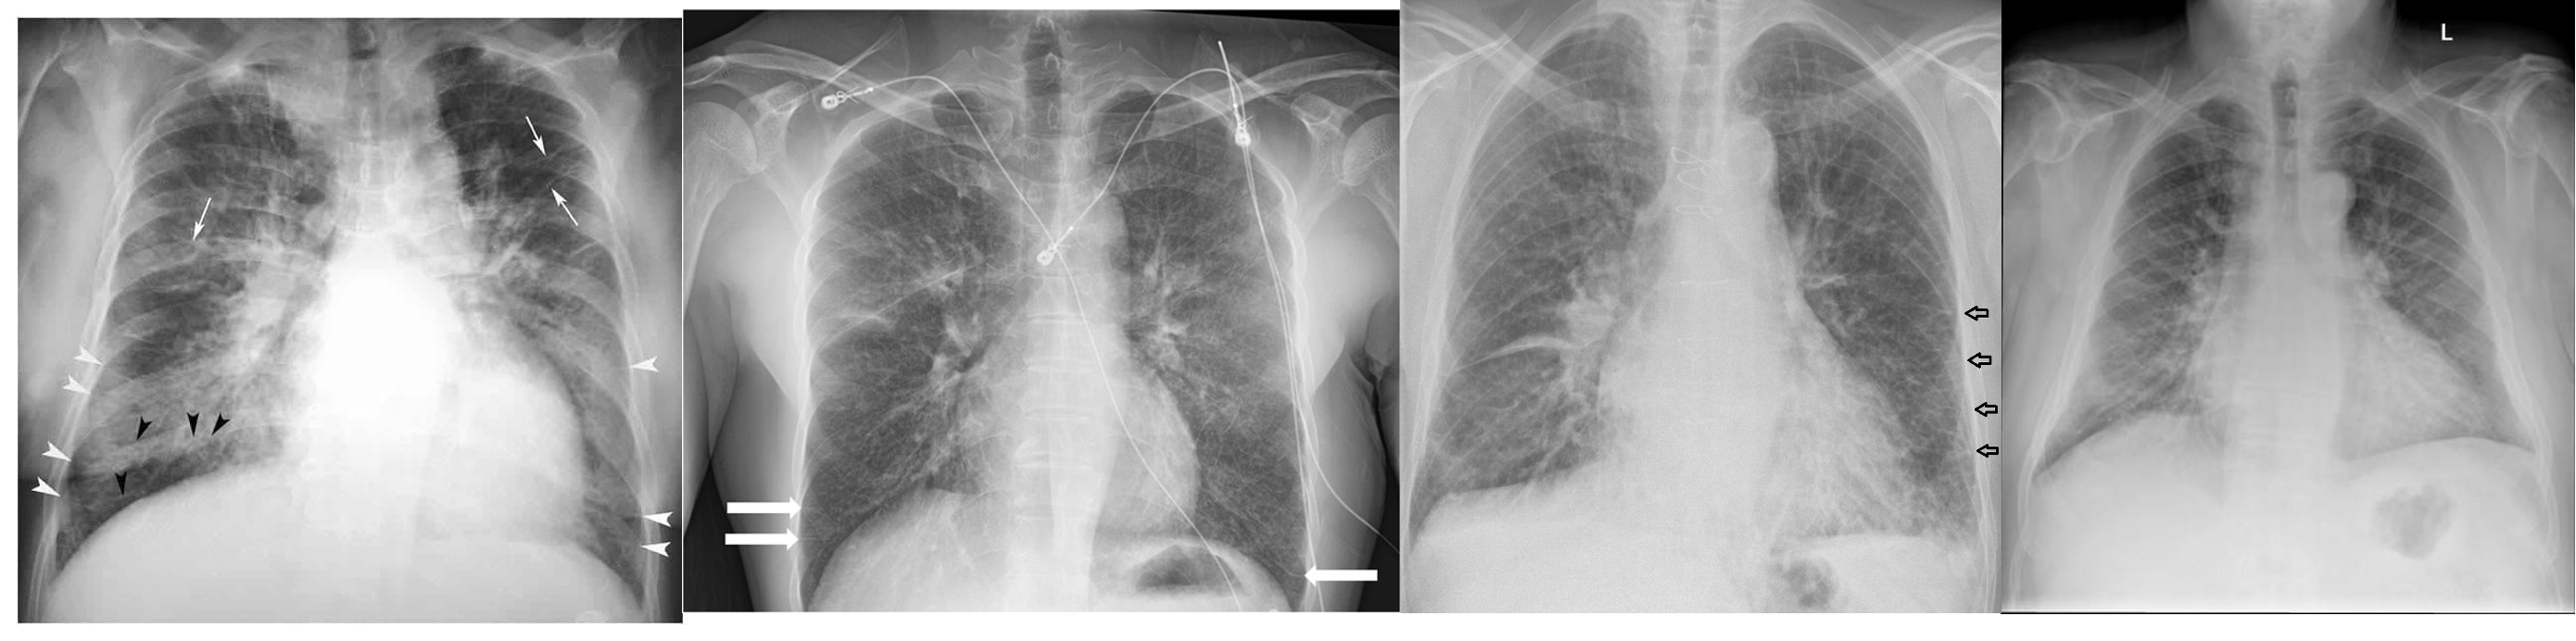

(Image: Cardiomegaly & pulmonary edema)

Cardiomegaly & pulmonary edema

- Cardiomegaly (not in diastolic failure)

- Pulmonary edema

- Pleural effusion

HOW TO CALCULATE CARDIOMEGALY ON CHEST X RAY

Horizontal diameter of the heart divided by the widest horizontal distance in the chest cavity.

If more than 0.5 → cardiomegaly (How to remember: heart/chest)